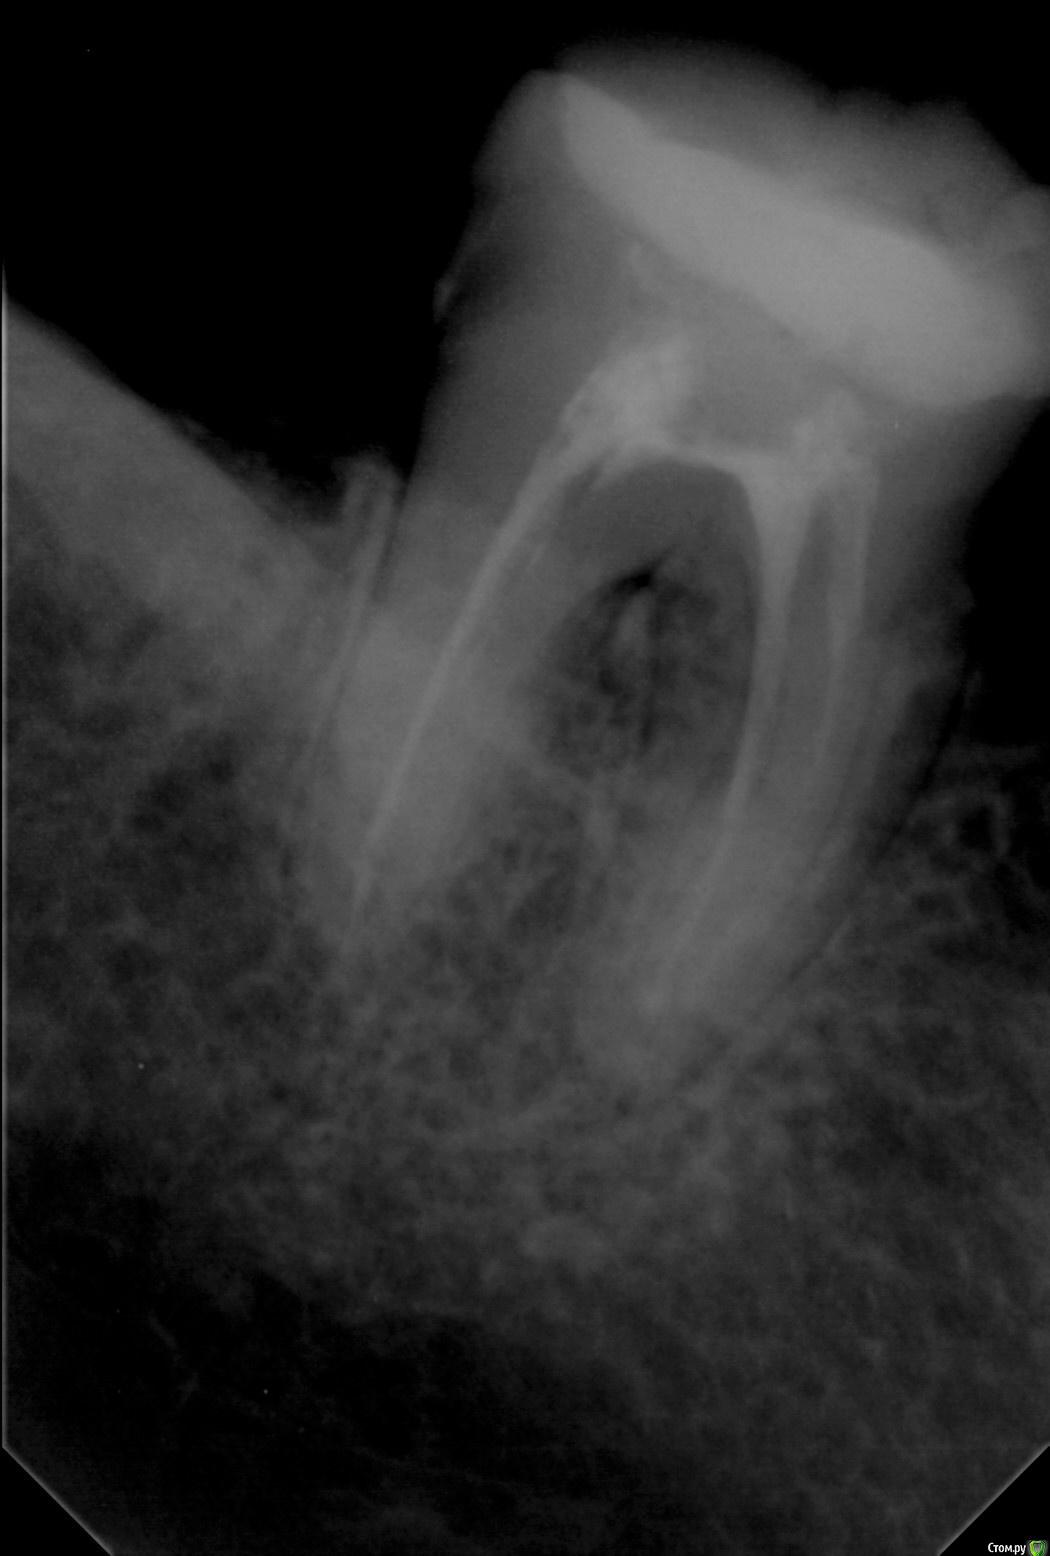

Wedernikoff Опубликовано 4 октября, 2017 Поделиться Опубликовано 4 октября, 2017 Здравствуйте, уважаемые доктора. Благодарю вас весх за терпение, тактичность и понимание.Моя проблема: НЧ, хочу бюгель на кламмерах. Стоит 47 зуб, снимок которорого приложен.Он как бы шактий-валкий, но с отлично пролеченными корнями. При этом есть небольшое (цитата врачей) воспаление между корней.В одной клинике его предлжили "подчистить", сделать вкладку, поставить коронку. И потом нацепить на него кламмер.Выбирать тут просто ..эээ.. не из кого. Реально. Делать буду протез в другом городе у дока с отзывами, у которого дорого и есть чудесная репутация. Не суть, сорри за оффтоп.Мои вопросы:нужна ли 7-ка эта под кламмер и критична ли вообще для бюгеля? А если её не будет, то какова судьба 44 и 35 с кламмерами на них? Выдержит ли долго такая семёрка ? И если полагаете, что да, то сначала коронка (вкладка), а потом только слепки? Или какова последовательность? Заранее благодарю вас, уважаемые доктора.Хорошего дня и всем +50000 солнечных лучиков к карме Ссылка на комментарий

Doc Опубликовано 4 октября, 2017 Поделиться Опубликовано 4 октября, 2017 Этот зуб даже под простую коронку пойдет без гарантии, а под бюгель и подавно не стоит.А почему не поставить пару имплантов с каждой стороны и не забыть про эту челюсть на долгие годы? 2 Ссылка на комментарий